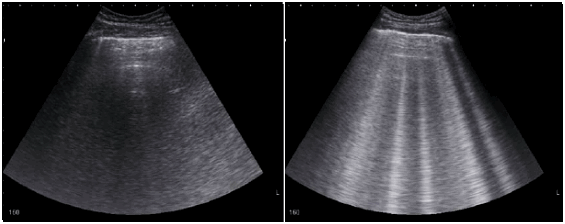

• Эхокардиография: сократимость левого желудочка снижена (ФВЛЖ <40%) или сохранена (ФВЛЖ ≥50%), расслабление левого желудочка нарушено.

• Рентгенография, ультразвуковое исследование грудной клетки: застой в легких.